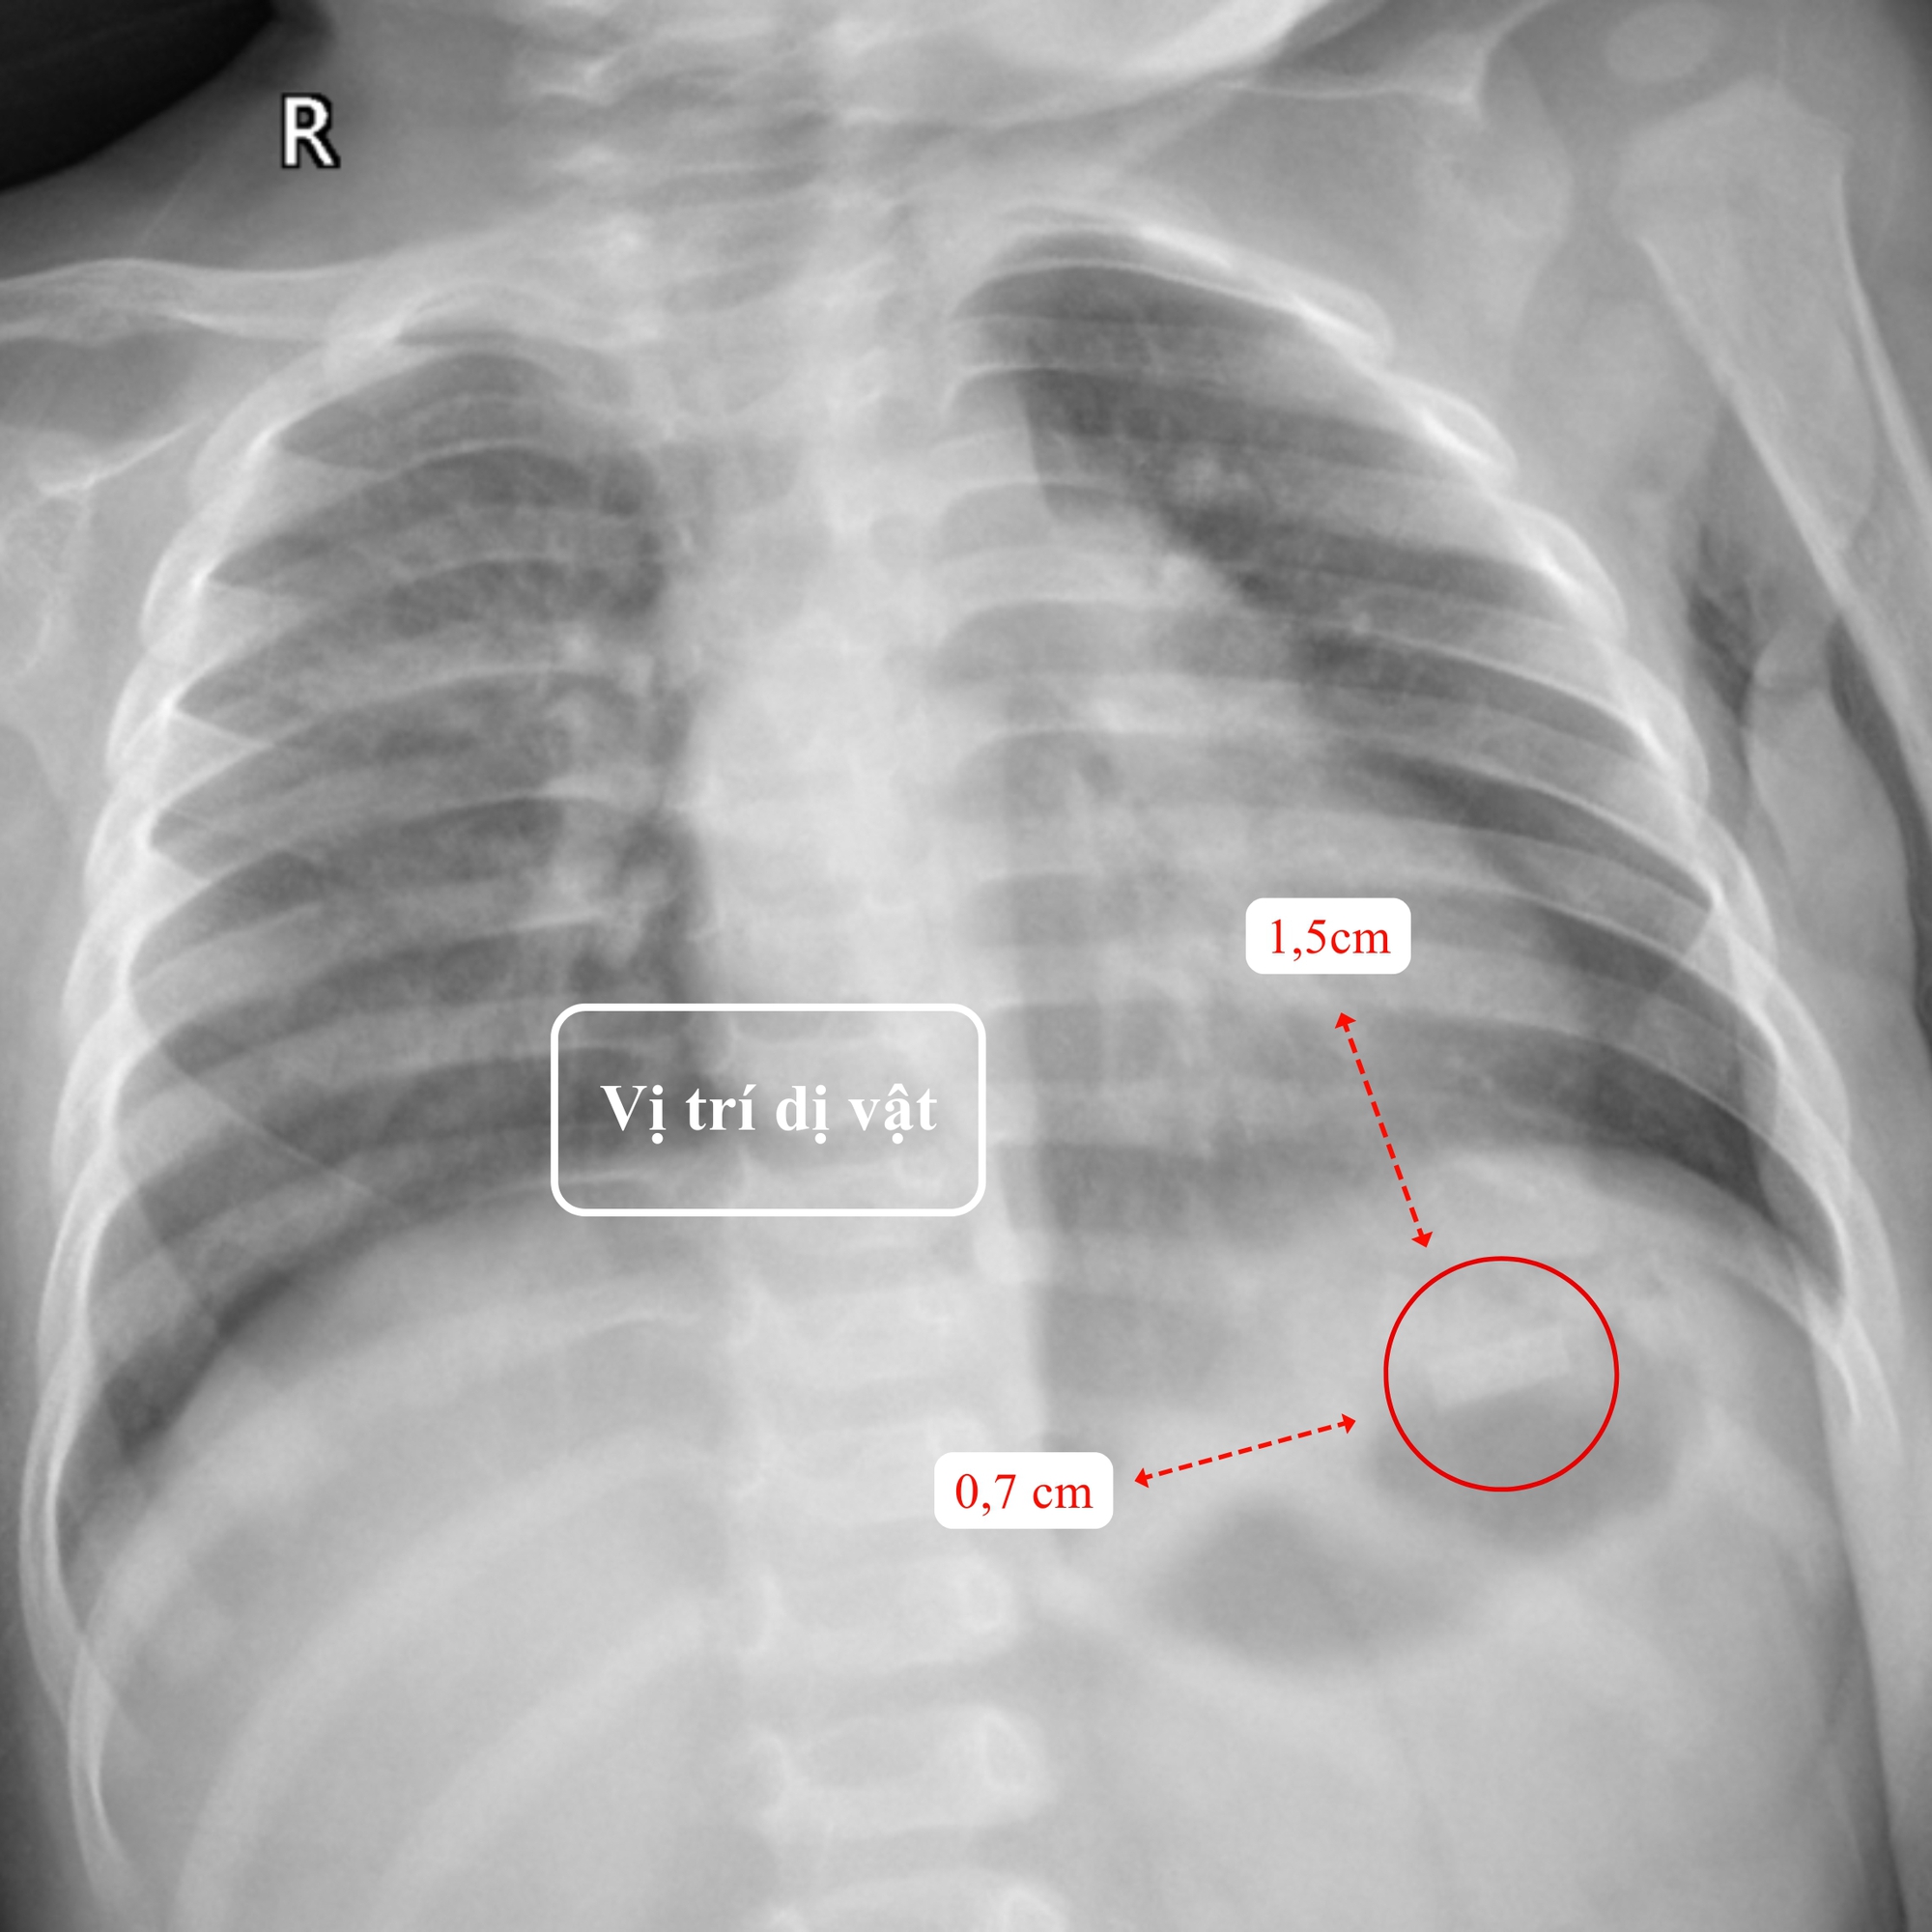

Tại Khoa Nhi - BVĐK Hồng Ngọc- Phúc Trường Minh, kết quả thăm khám lâm sàng và cận lâm sàng cho thấy một dị vật kim loại hình chữ nhật kích thước 1,5x0,7cm, có góc nhọn, mỏng và sắc như lưỡi dao nằm tại vùng hạ sườn trái, vị trí bóng hơi dạ dày của bé T. Ngoài ra, do nuốt phải một phần thuốc lá, trẻ có biểu hiện say thuốc với triệu chứng mệt mỏi, môi tái. Song, tình trạng này chỉ kéo dài khoảng 30 phút. Sau theo dõi, các chỉ số sinh tồn của bé ổn định, xét nghiệm máu không phát hiện bất thường.

Vị trí dị vật trên film chụp X-quang